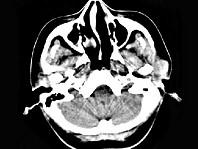

问题 女,28岁,左耳前肿块34月余,PE:左侧耳前可触及肿块,境界尚清、质硬、活动度尚可,CT如图所示,最可能诊断为()

选项 A.神经纤维瘤 B.腮腺恶性混合瘤 C.腮腺腺淋巴瘤 D.副神经节瘤 E.腮腺混合瘤

答案 E